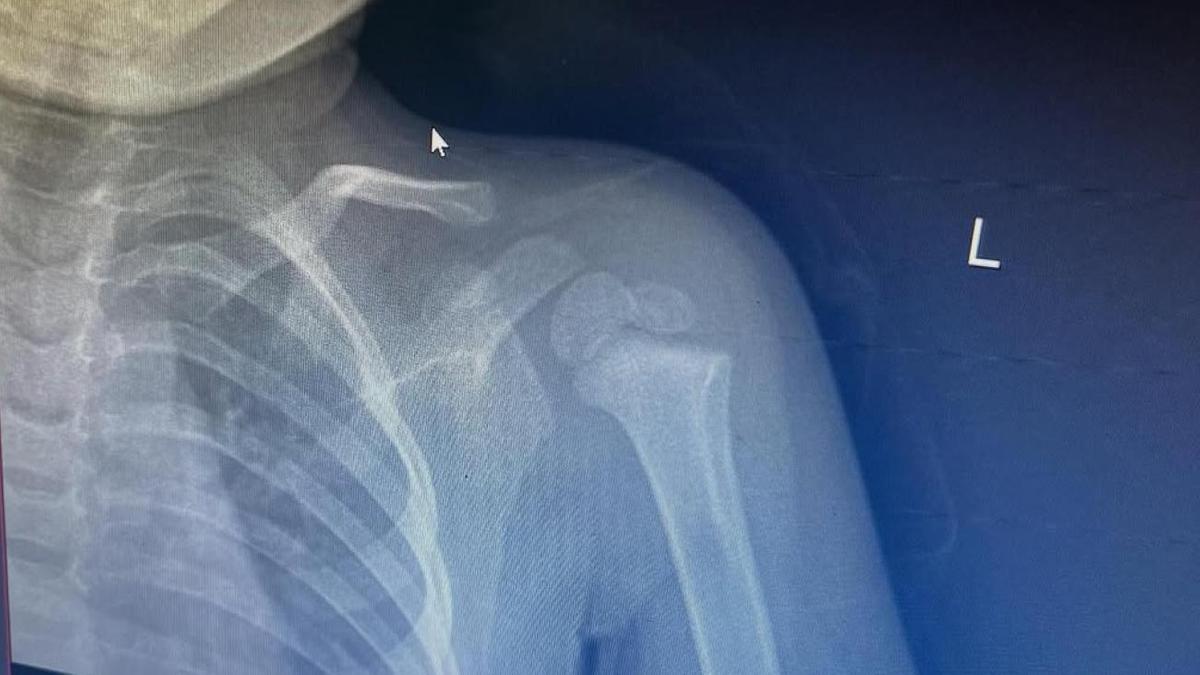

Сегодня мы писали, что в Сети появилось видео, где подросток, вероятно, ударил о землю двухлетнего ребенка - пострадавший сломал руку. Мать малыша рассказала подробности.